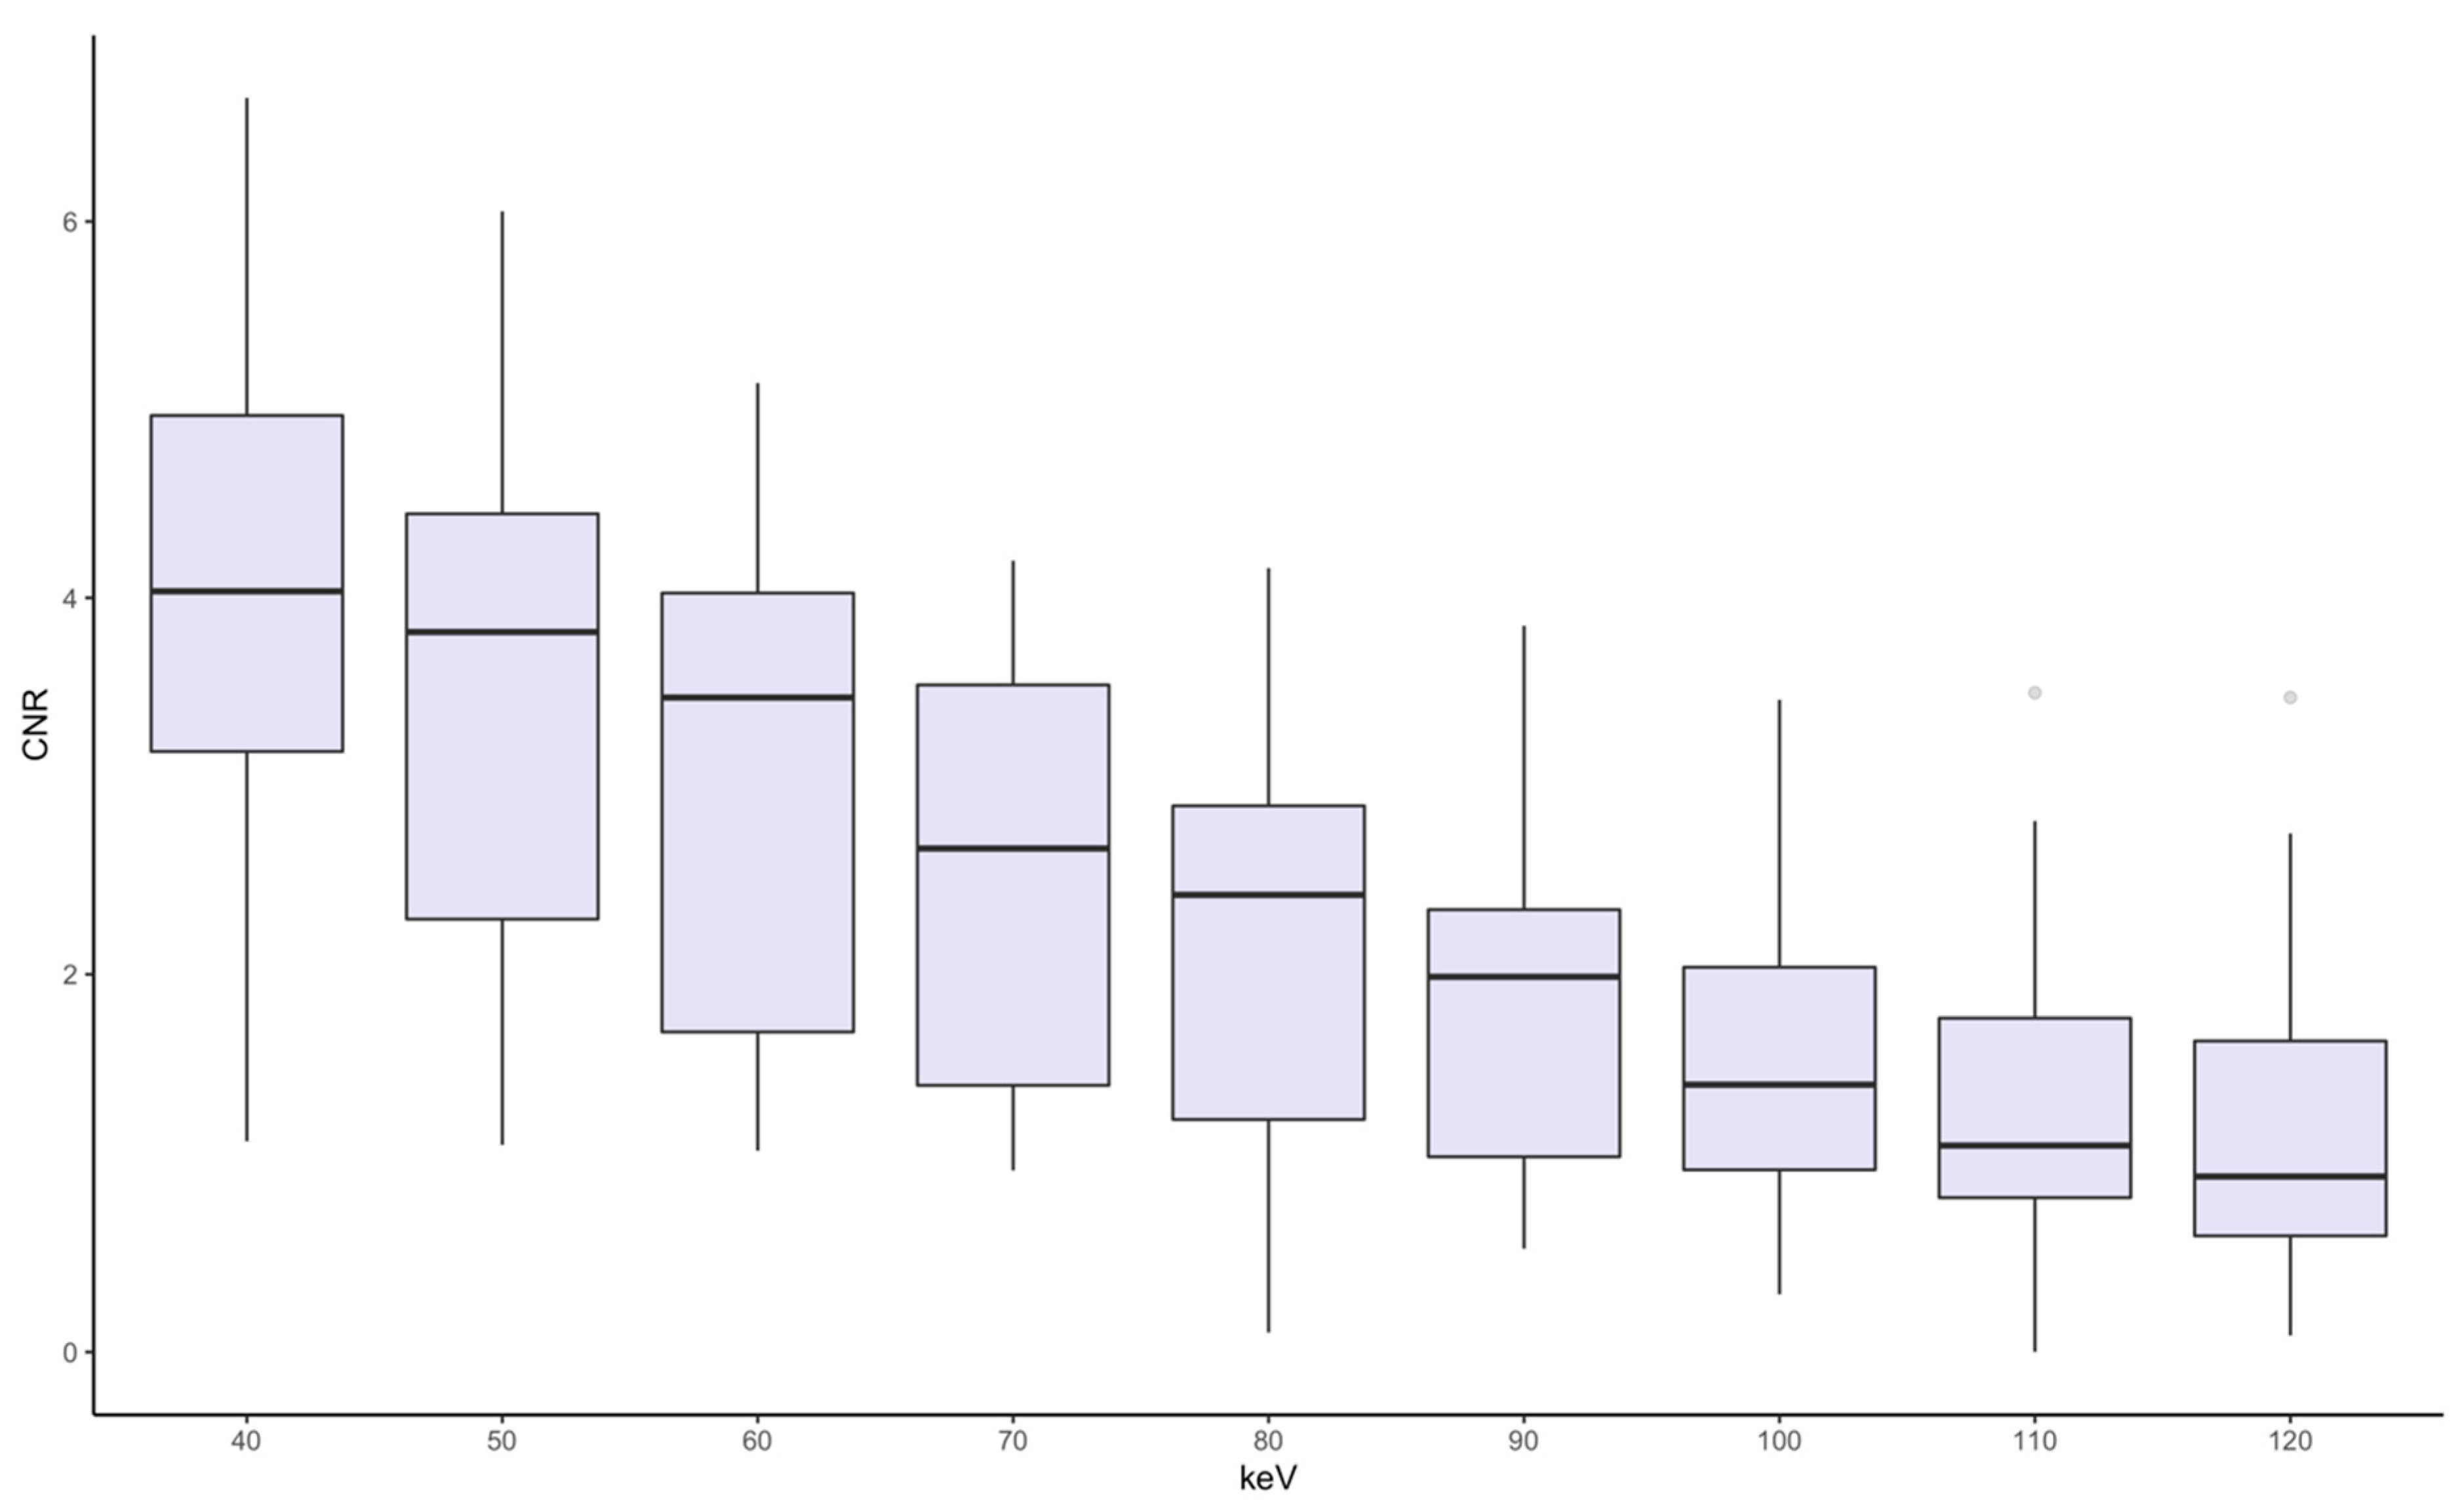

3.2. Quantitative Image Analysis

3.3. Qualitative Image Analysis